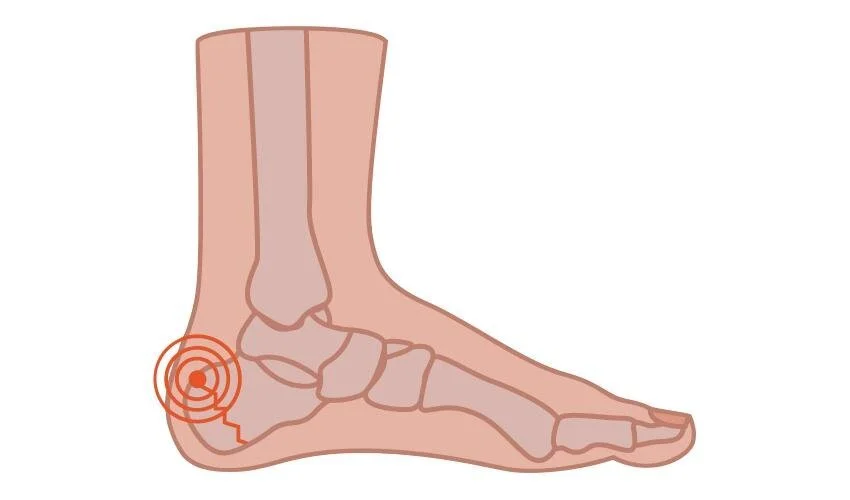

Plantar Fasciitis/Heel Spur Syndrome

Plantar Fasciitis is the painful inflammation of a band beneath the heel and arch that inserts at the base of the toes. Plantar fasciitis is what is most commonly called but can also be called Plantar Fasciosis. One of the most common foot problems a Podiatrist treats and affects 10% of the population.